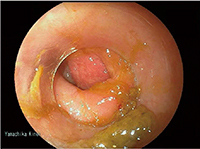

当院の大腸内視鏡検査では痛みが強く,下行結腸途中までの検査になってしまったが,S状結腸にType2の進行がんを思わせる隆起性病変(図5)が認められ,下行結腸途中から全周性の発赤で易出血性であった。大腸内視鏡検査より潰瘍性大腸炎を発生母地としたcolitic cancerを疑い,下行結腸から口側の大腸と血管分岐の情報を得るためにCT angiographyを含めた大腸CT検査が行われた。

図5 大腸内視鏡画像

大腸CT検査では,上行結腸から下行結腸途中にかけての粗造な粘膜変化と壁の肥厚,S状結腸に中心陥凹の隆起性病変が認められた。粘膜の変化は上行結腸途中まで見られ,盲腸部は正常と思われた。また,隆起性病変付近のS状結腸は,潰瘍性大腸炎の特徴の一つであるハウストラの消失(鉛管像)が見られた(図6)。